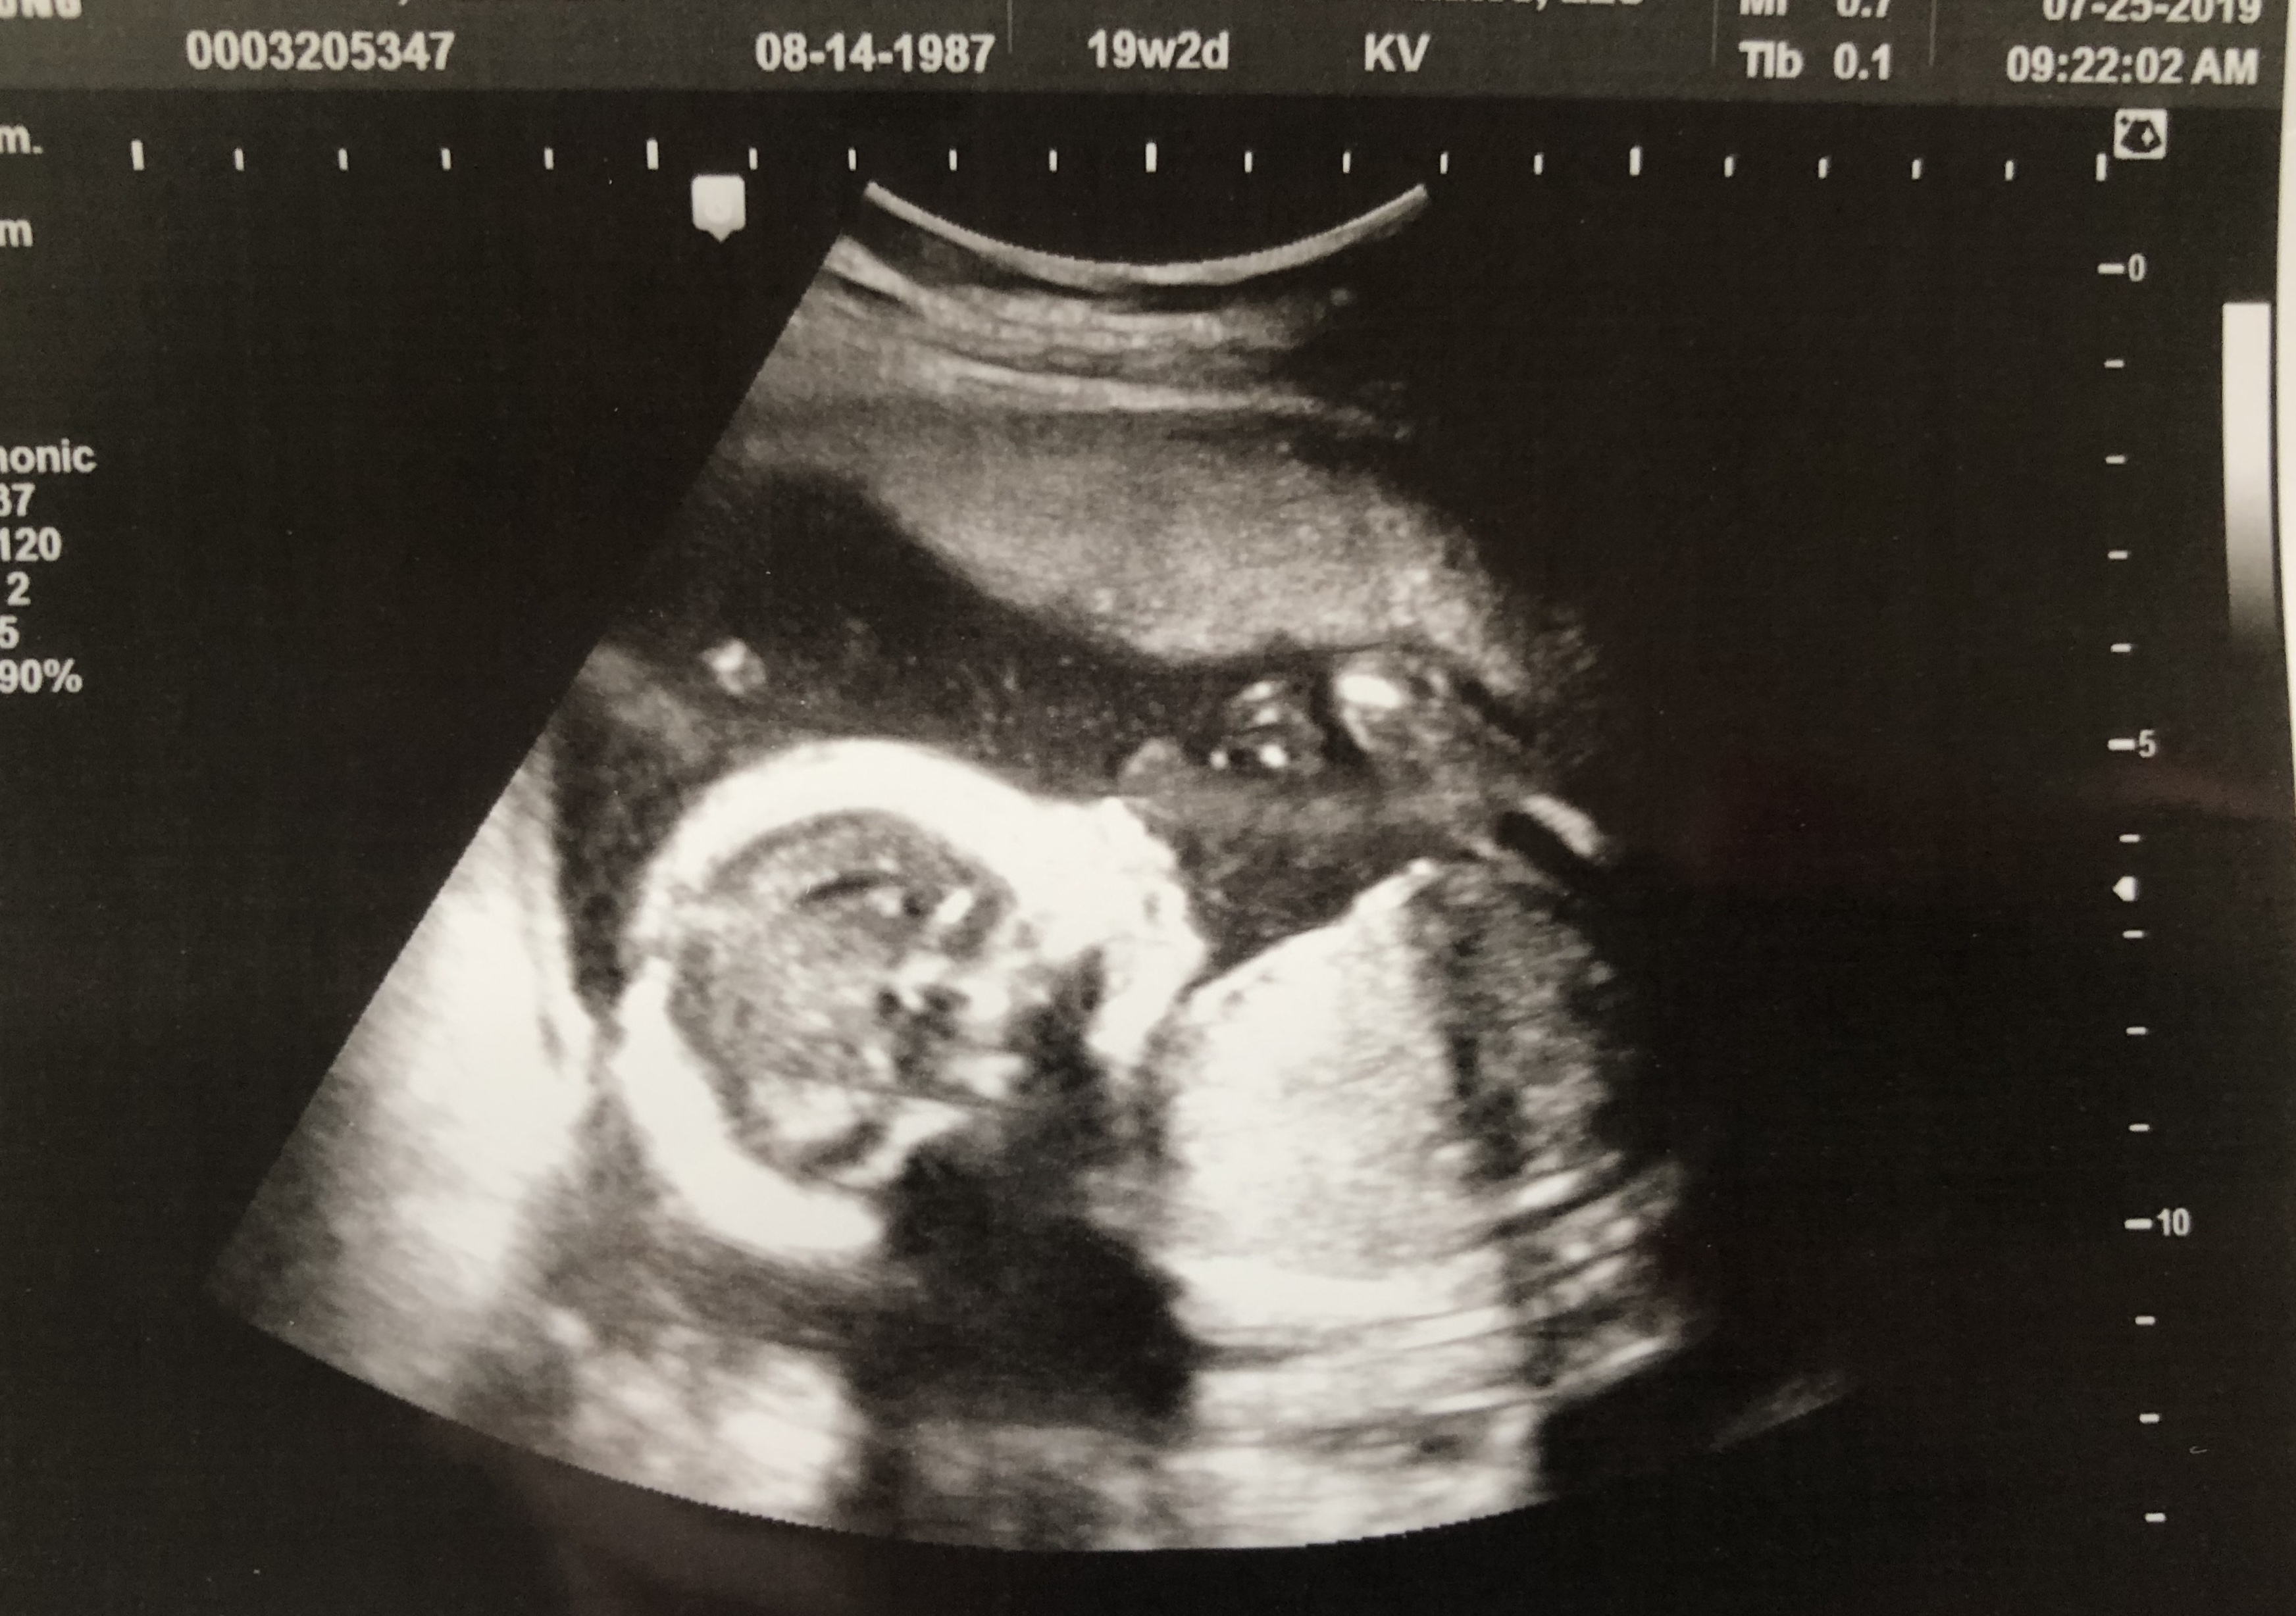

My OB couldn't find the heartbeat with the doppler so I had to get an ultrasound today. After some panic, I got to see that baby boy is doing great. Heart rate of 153 and measuring at 16w2d exactly.